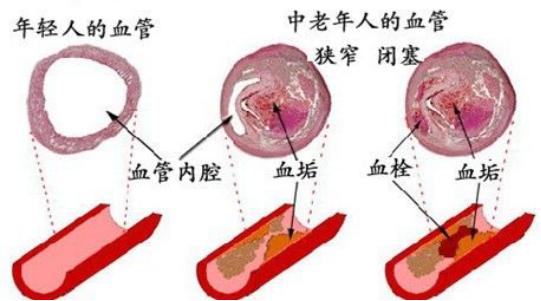

そして、アテローム性動脈硬化プラークは一般的な慢性病変であり、その発生と発症は高血圧、糖尿病、高脂血症などの多くの要因に影響される。長期にわたる高血圧、高血糖、高脂血症を管理しないと、人体各部の動脈に動脈硬化性プラークが発生しやすくなり、この動脈硬化性プラークが脳動脈に発生すると、脳血栓症発生の下地を作ることになる。たとえば、時間の経過とともに、血圧、血糖、血中脂質がまだコントロールされていない、アテローム性プラークがますます大きくなり、ますます不安定になり、この時、アテローム性プラークが大きくなりすぎたり、突然破裂したりすると、その場で血栓症が発生し、動脈血管が閉塞し、脳梗塞も発生する。

人体を例にとって言えば、水道管の老化は動脈硬化のようなもので、動脈硬化がプラークを生成するのは「さび色の斑点」、「汚れ」のようなものだ。

違いは、プラークが破裂して血栓症を促進する可能性があることで、これが心血管疾患の急性発作の原因である。

実際、血栓症は防御機構である:

例えば、皮膚が破れて出血した場合、出血は自動的に止まるが、これは血栓症の結果である。 血栓が形成され、破れを塞ぐことで出血が止まるのである。しかし、この破断は血管のプラーク上で起こり、破断した場所から自ら修復して血栓が形成されるが、血管局所では限られたスペースしかないため、血管の局所的な狭窄、あるいは閉塞を引き起こす。

頸動脈は、重度のプラーク、つまり不安定プラークが発生すると、一度破裂したプラークが血栓を形成し、この血栓が脳血管に流れて脳血管を閉塞し、脳梗塞を引き起こす。

頸動脈プラークが形成される主な理由は動脈硬化であり、動脈硬化が形成される主な理由は、不健康な食事、喫煙と飲酒、肥満、運動不足の座りっぱなし、プレッシャーの多い徹夜、コントロールできない三高、遺伝的理由などである。特に不健康な生活と三高に注意しないと、動脈硬化が加速する。だから、動脈硬化の予防は、子供の頃から健康的な生活習慣を身につけることである。